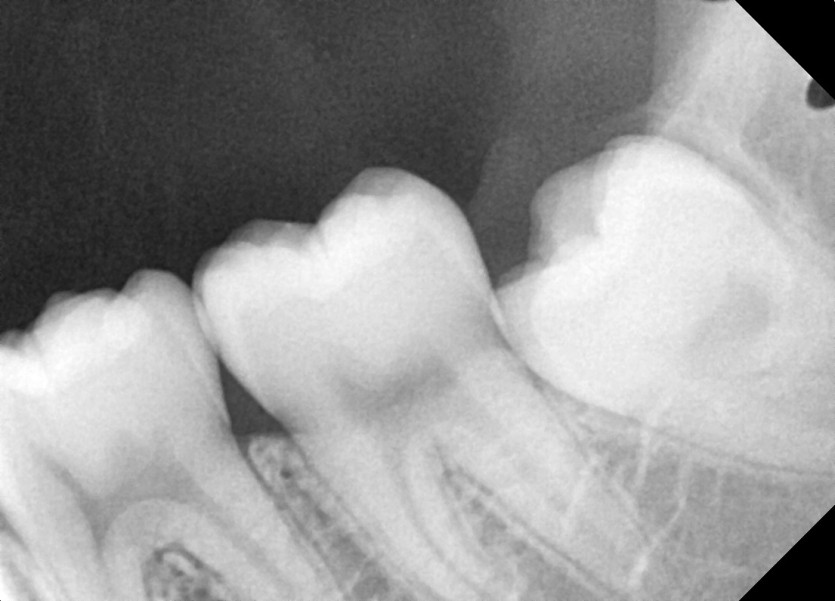

#28,38 사랑니 발치

구강 외과 전문의가 당일 발치했습니다.